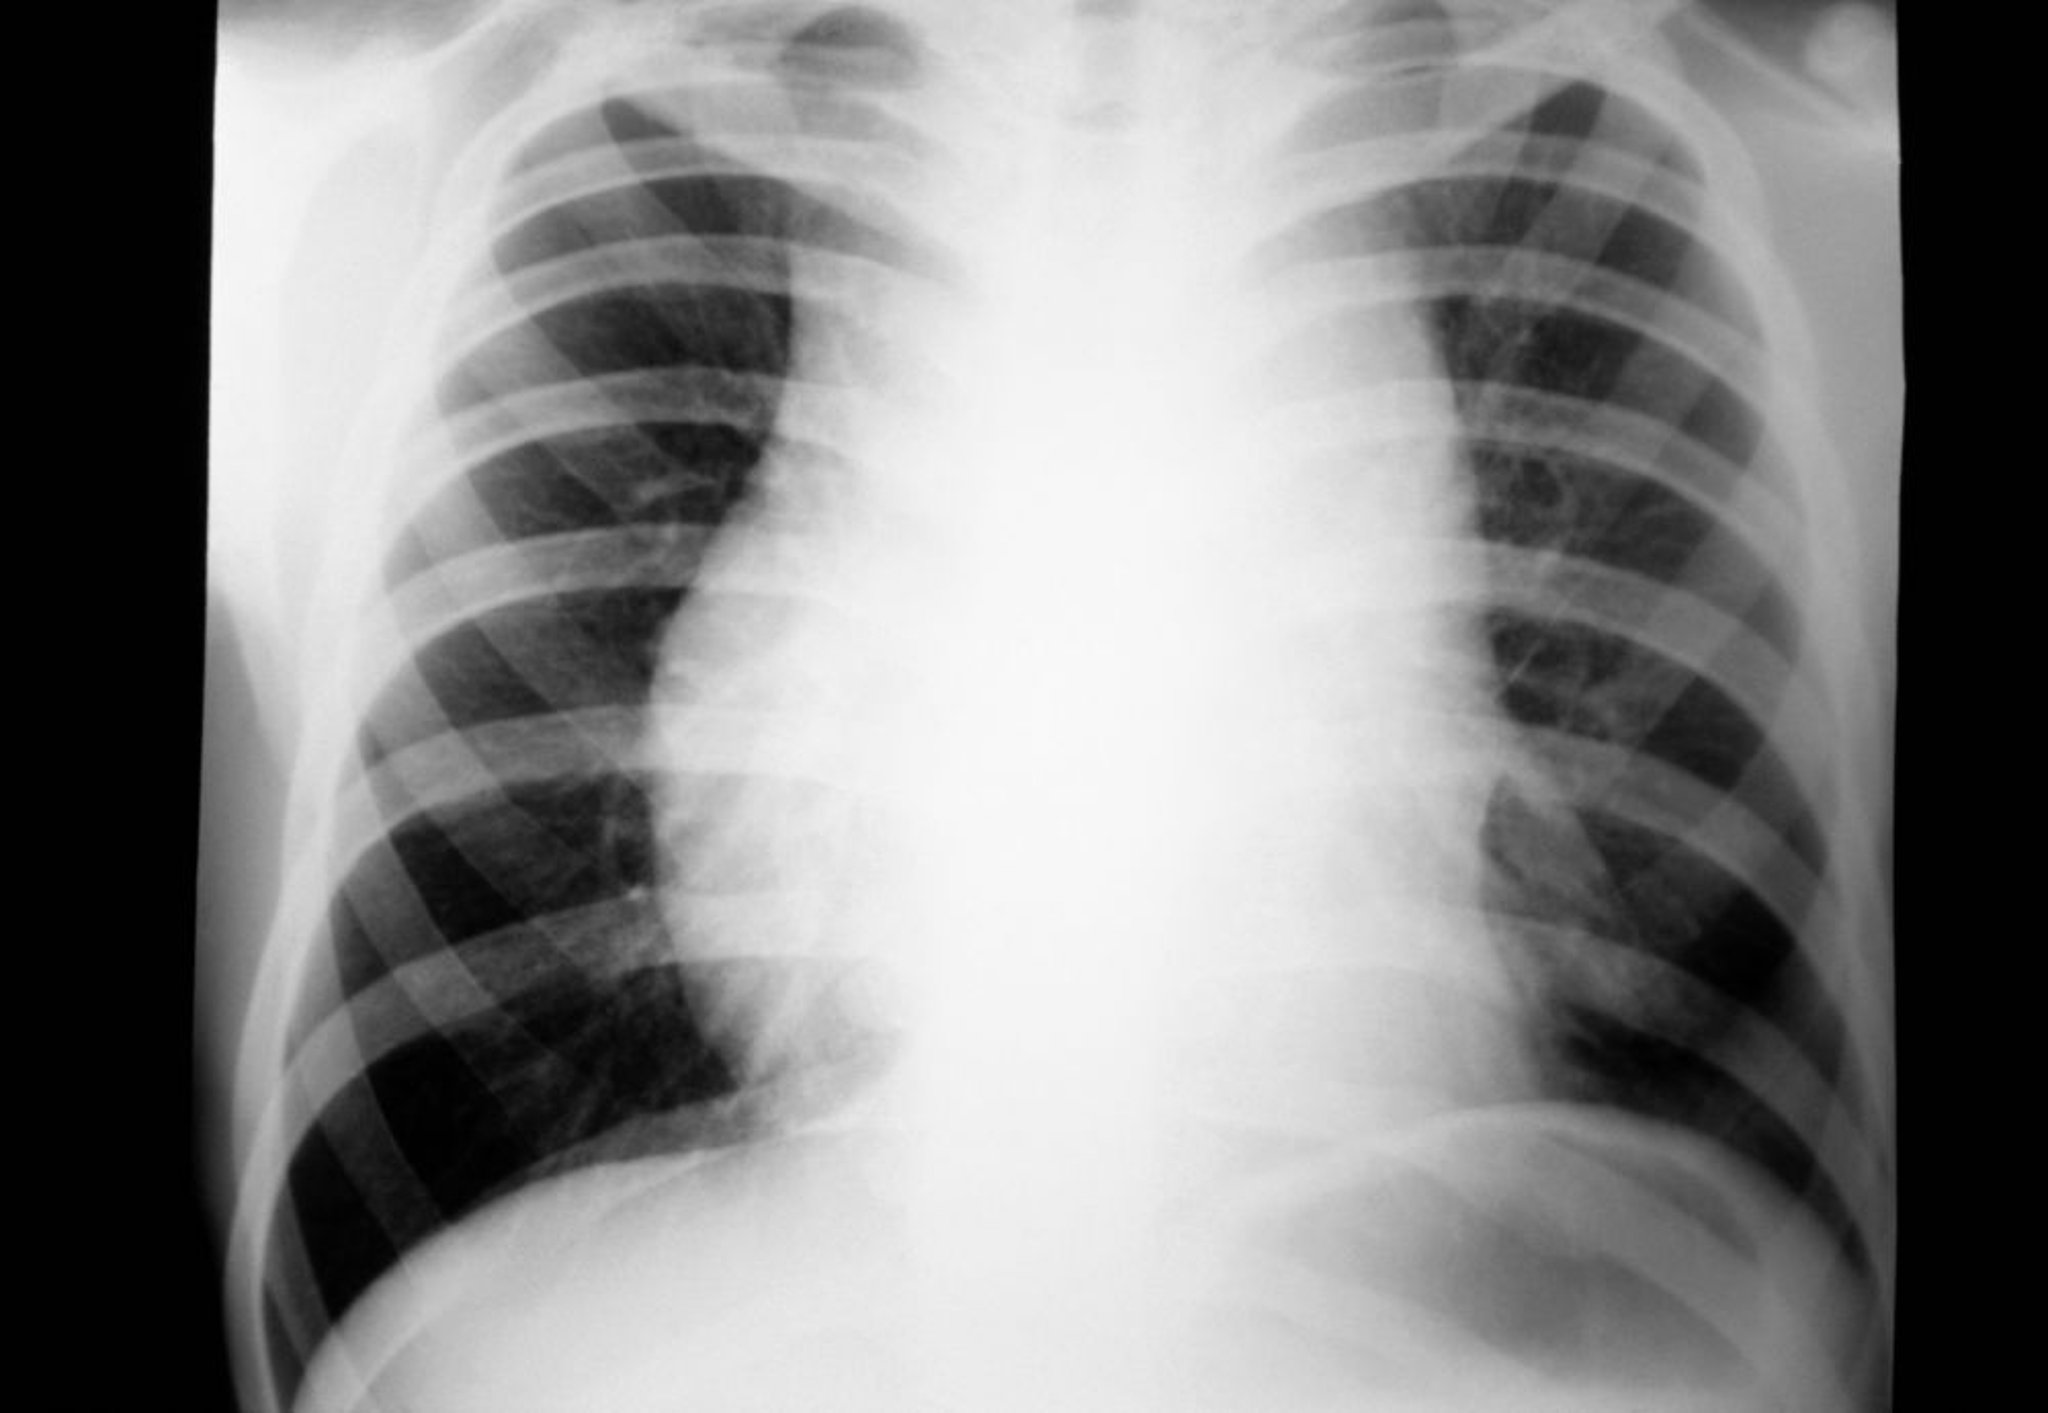

Hodgkin-Lymphom (mediastinale Lymphadenopathie)

Röntgenthorax eines Patienten mit Hodgkin-Lymphom mit mediastinaler Lymphadenopathie.